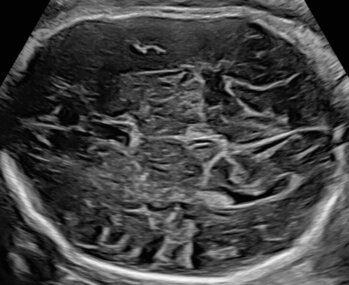

Ultraschalluntersuchung der mütterlichen und kindlichen Durchblutung (Farb-Dopplersonografie)

Die Durchblutung der Nabelschnur, der kindlichen Gefäße und des Mutterkuchens wird mittels einer speziellen Ultraschalltechnik durchgeführt. Mit der sogenannten (Farb-)Dopplersonografie können wir in der Pränataldiagnostik und Schwangerenambulanz die Versorgungslage überprüfen.

Auffällige Blutflussmuster können auf eine Mangelversorgung des Ungeborenen oder Auffälligkeiten im Kreislauf der Mutter hinweisen. Zu nennen wäre hier das erhöhte Risiko für einen schwangerschaftsbedingten Bluthochdruck. Mittels der Untersuchung können solche Probleme rechtzeitig erkannt und die Patientin entsprechend am UKS überwacht werden.